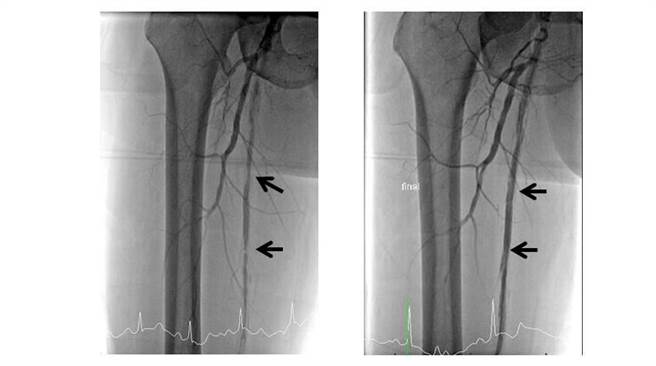

61岁朱姓男子术前及术后影像。(丰原医院提供)

61岁朱姓男子有高血压、糖尿病、高血脂以及末期肾臟疾病病史,因右脚背伤口裂开,合併有发红、肿胀、异常疼痛,诊断是右脚蜂窝性组织炎,因伤口癒合差,外科陈明泽主任检查后,及时发现病人右脚动脉血管有轻度阻塞,且双脚胫前动脉及腓动脉血管变得狭窄,立即照会心臟科医师张伟俊,给予右脚经皮气球血管扩张术(Percutaneous transluminal angioplastyPTA),并放置2支支架,术后右脚血液循环获得改善。